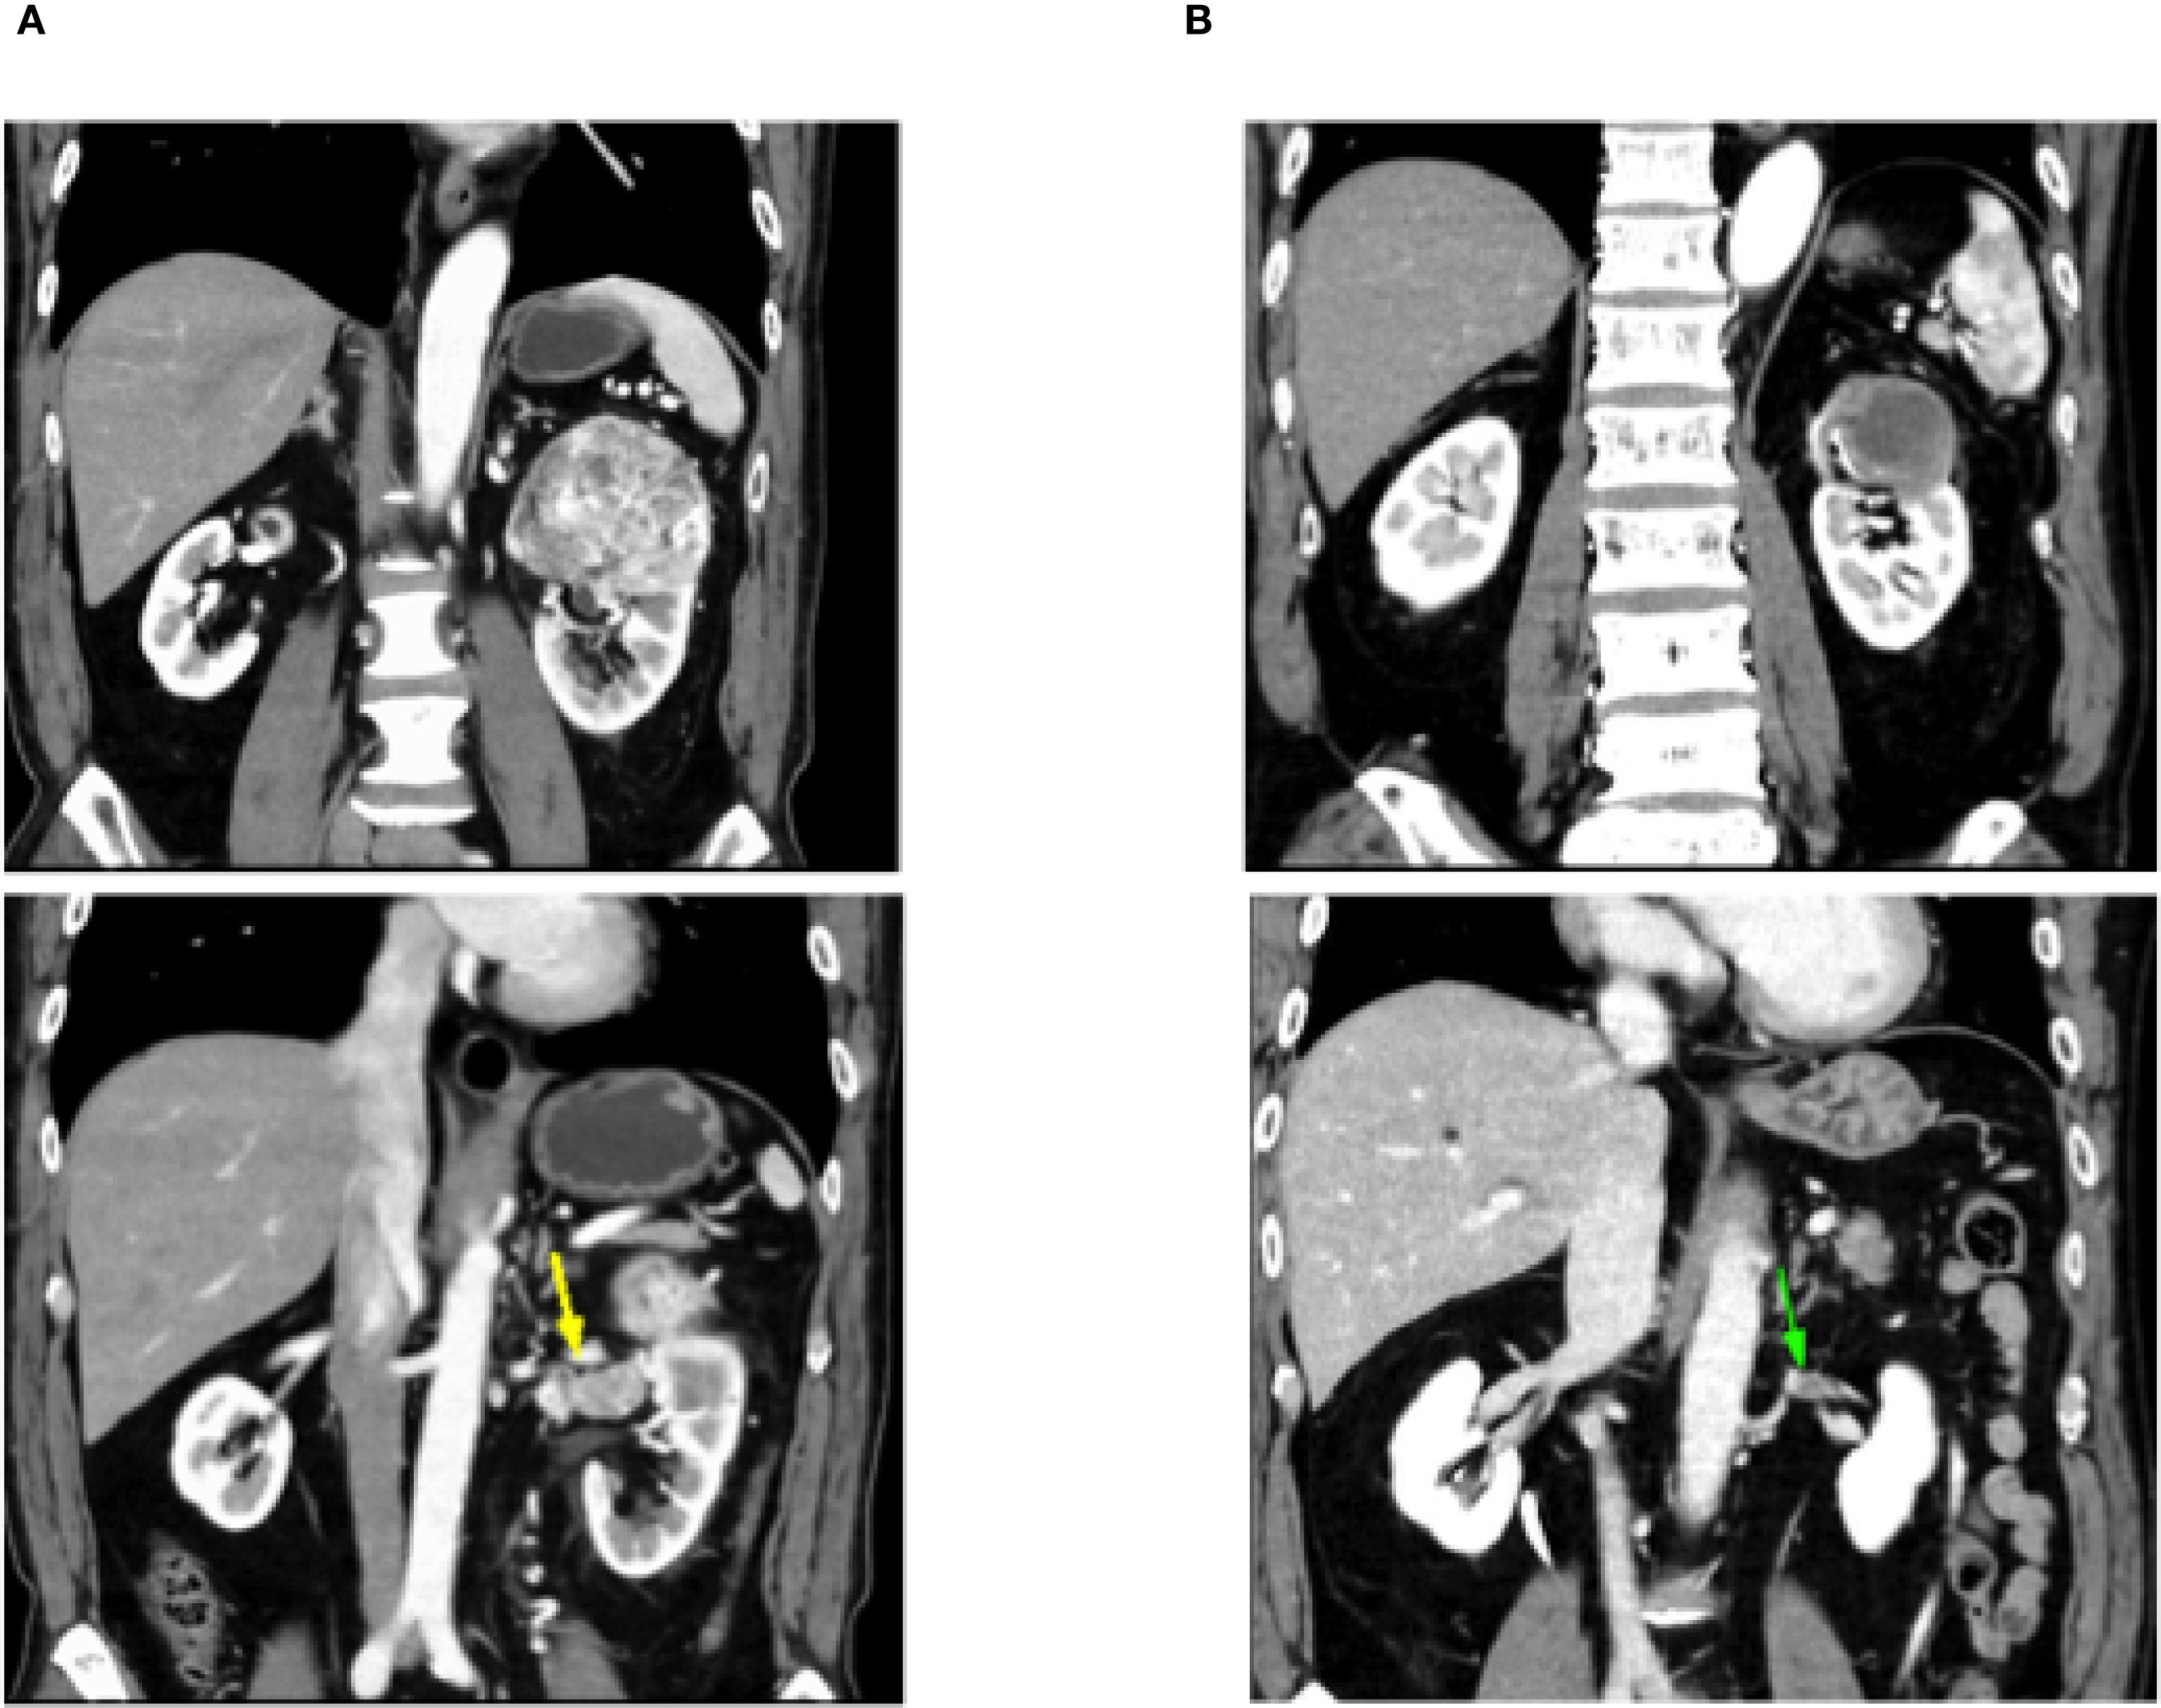

During treatment, he developed a grade 1 skin rash and grade 1 hoarseness, both of which were resolved with conservative management. Two months later, he developed grade 2 hypothyroidism, which was diagnosed as painless thyroiditis based on endocrine evaluation, including measurements of thyroid function (FT3, FT4), thyroid-stimulating hormone, and thyroid autoantibodies (anti-TPO, anti-thyroglobulin, and TRAb). Levothyroxine replacement therapy was initiated and titrated to maintain euthyroidism. A follow-up CT scan after five courses of SACT showed that the renal tumor had decreased in size from 80 × 60 mm to 47 × 35 mm, and the tumor thrombus had markedly regressed (Figure 1). The tumor was therefore considered resectable, and the patient underwent robot-assisted left nephrectomy and venous thrombectomy.

Figure 1. Follow-up computed tomography scan shows that the left renal tumor shrank from 80 × 60 mm to 47 × 35 mm and the tumor thrombus is markedly reduced. (A) CT before Nivolumab + cabozantinib. (B) CT after Nivolumab + cabozantinib.